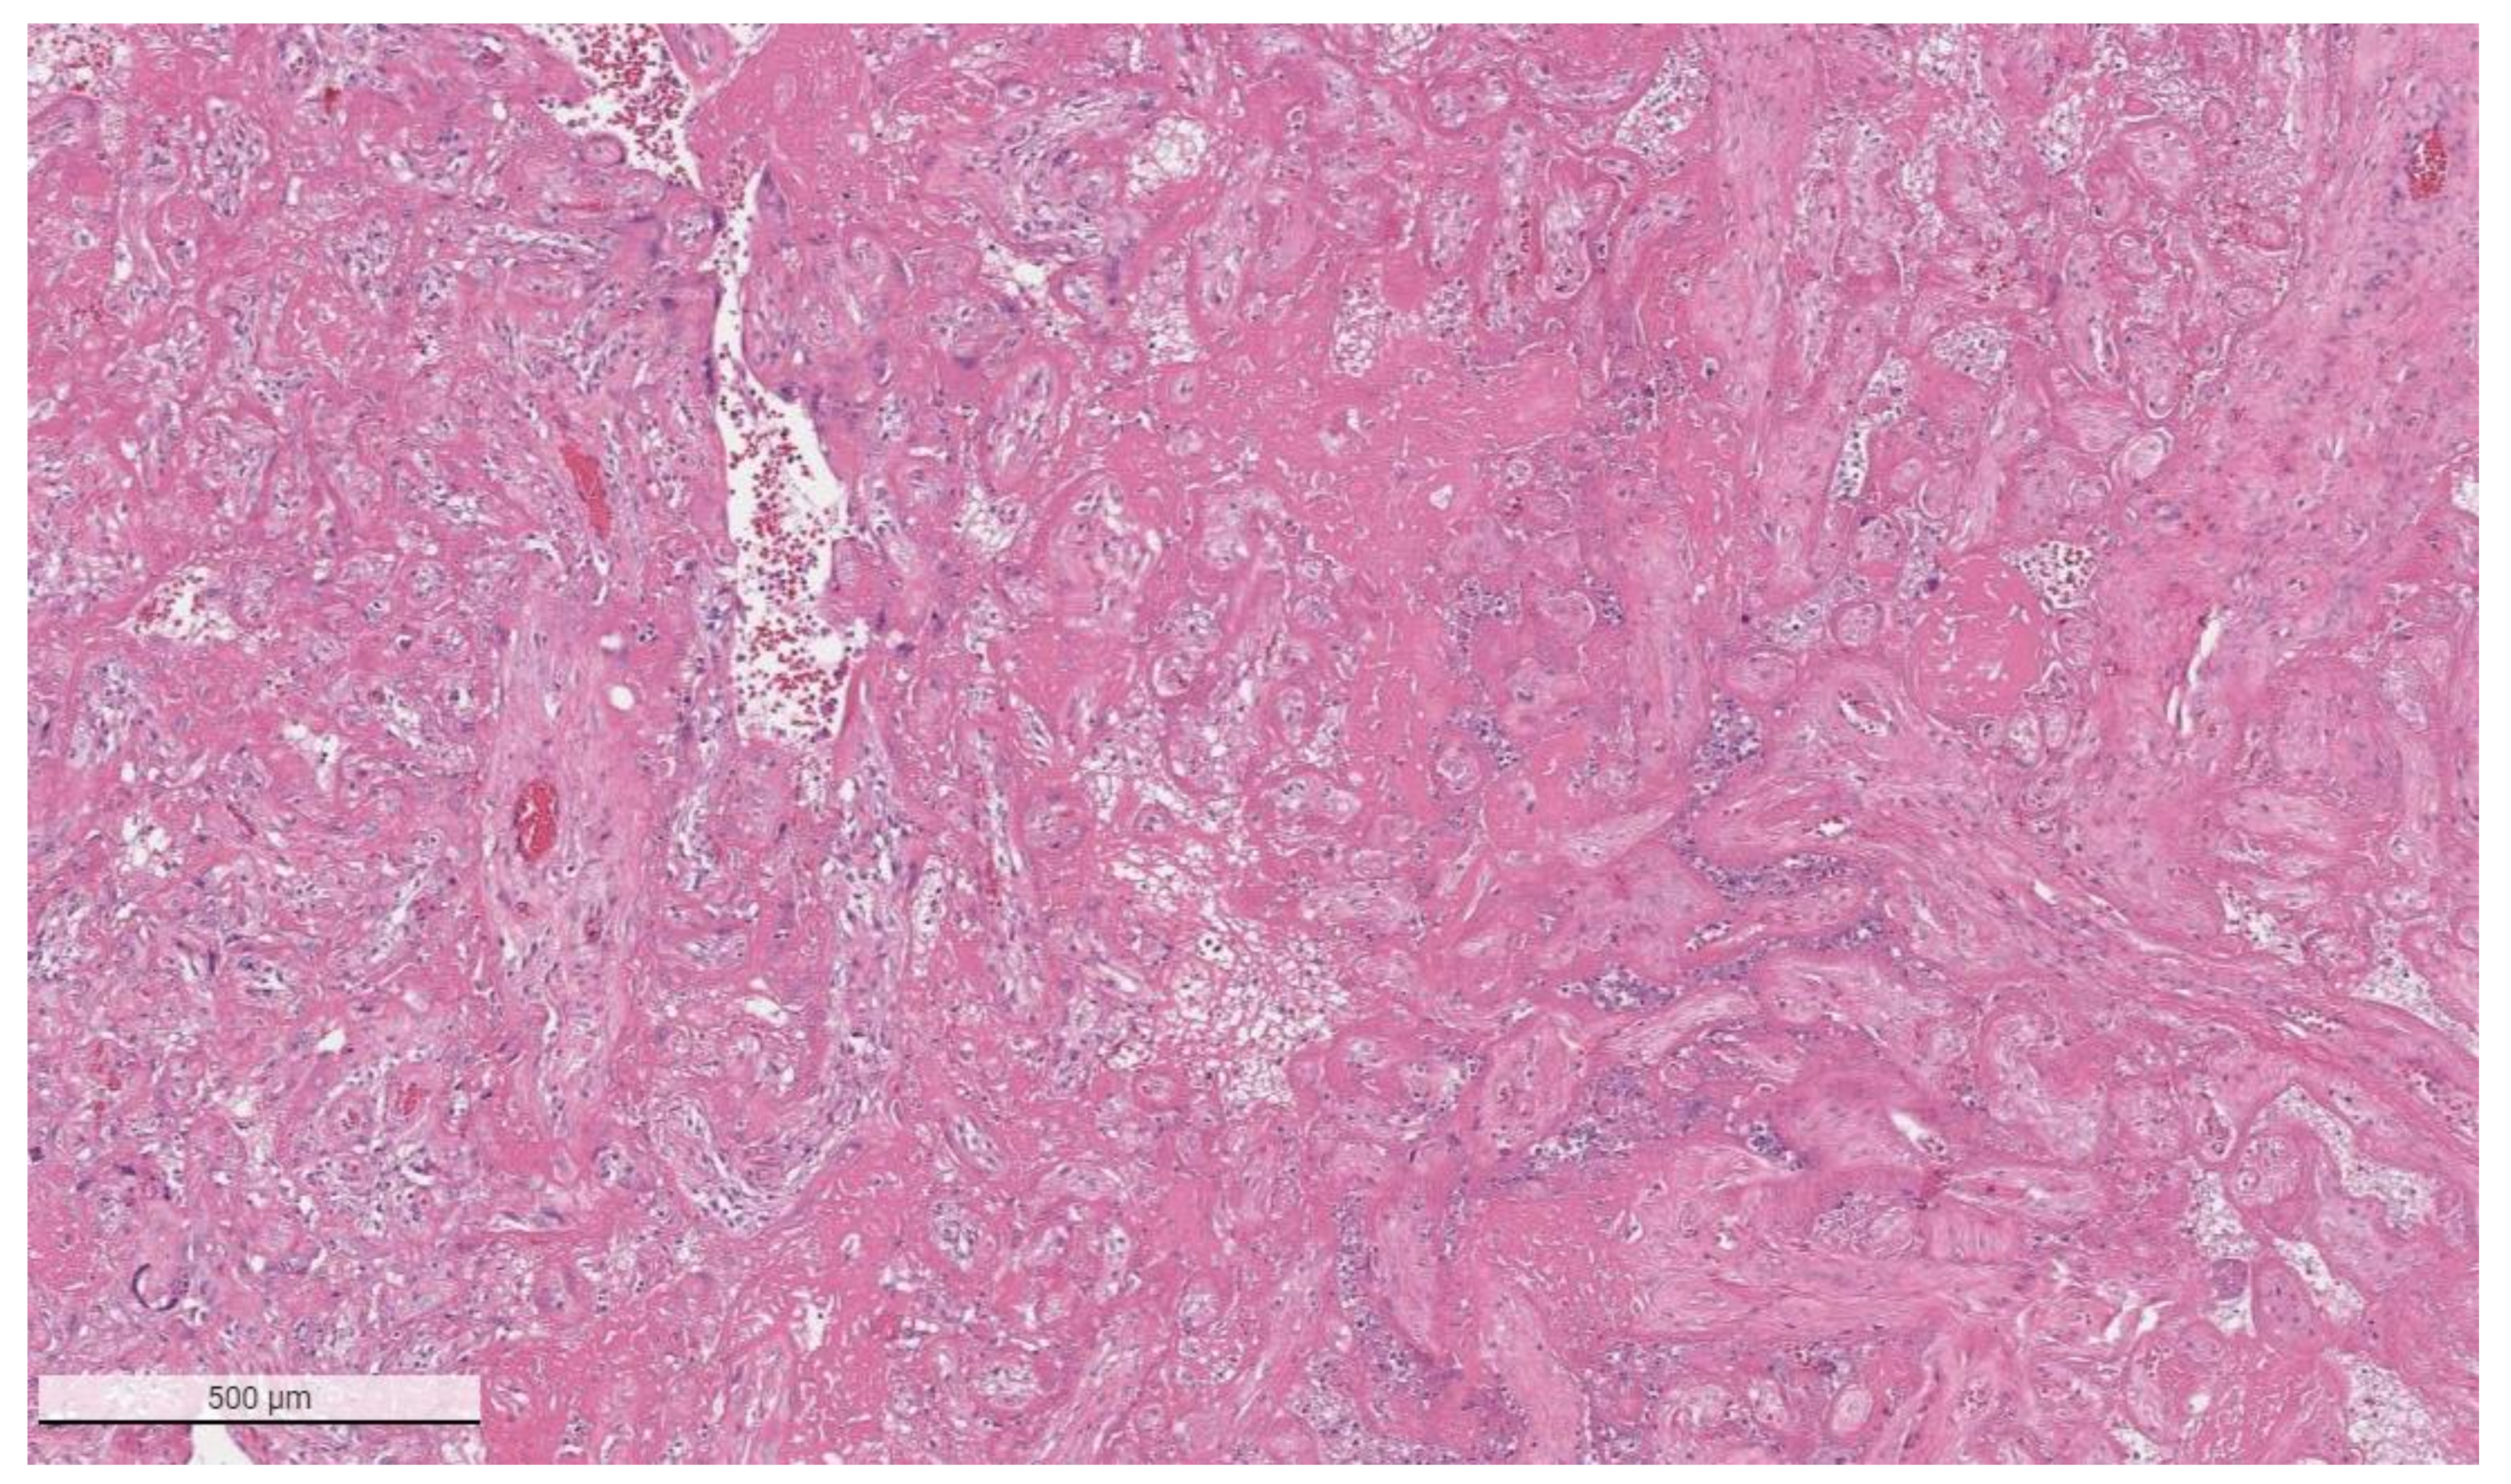

Figure 2.

Massive perivillous fibrin deposition in a placenta from a stillborn fetus delivered to a mother with COVID-19. This placenta was positive for SARS-CoV-2 and had greater than 90% tissue destruction. Hematoxylin & eosin staining, ×4.